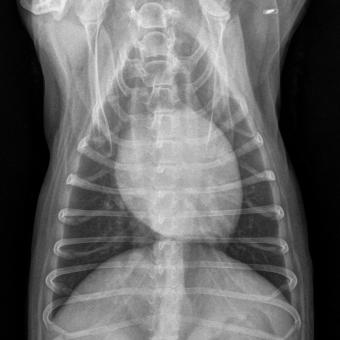

Eine Vergrösserung der Herz-Silhouette auf beiden Aufnahme-Ebenen des Brustkorbes – aber auch eine Verdichtung des Lungengewebes (Flüssigkeitsansammlung im Interstitium den Bronchien und Alveolen) sind ernste Zeichen und veranlassen entweder direkt einen Therapieversuch, oder führen zu den unten aufgeführten weiteren Untersuchungen.

Röntgenaufnahmen des Brustkorbes auf zwei Ebenen mit vergrössertem und abgerundetem Herzschatten und Verdichtung im Lungengewebe.

Thorax Röntgen

«Valentins-Herz»: Ventro-dorsale Aufnahme mit vergrösserter Herz- Silhouette